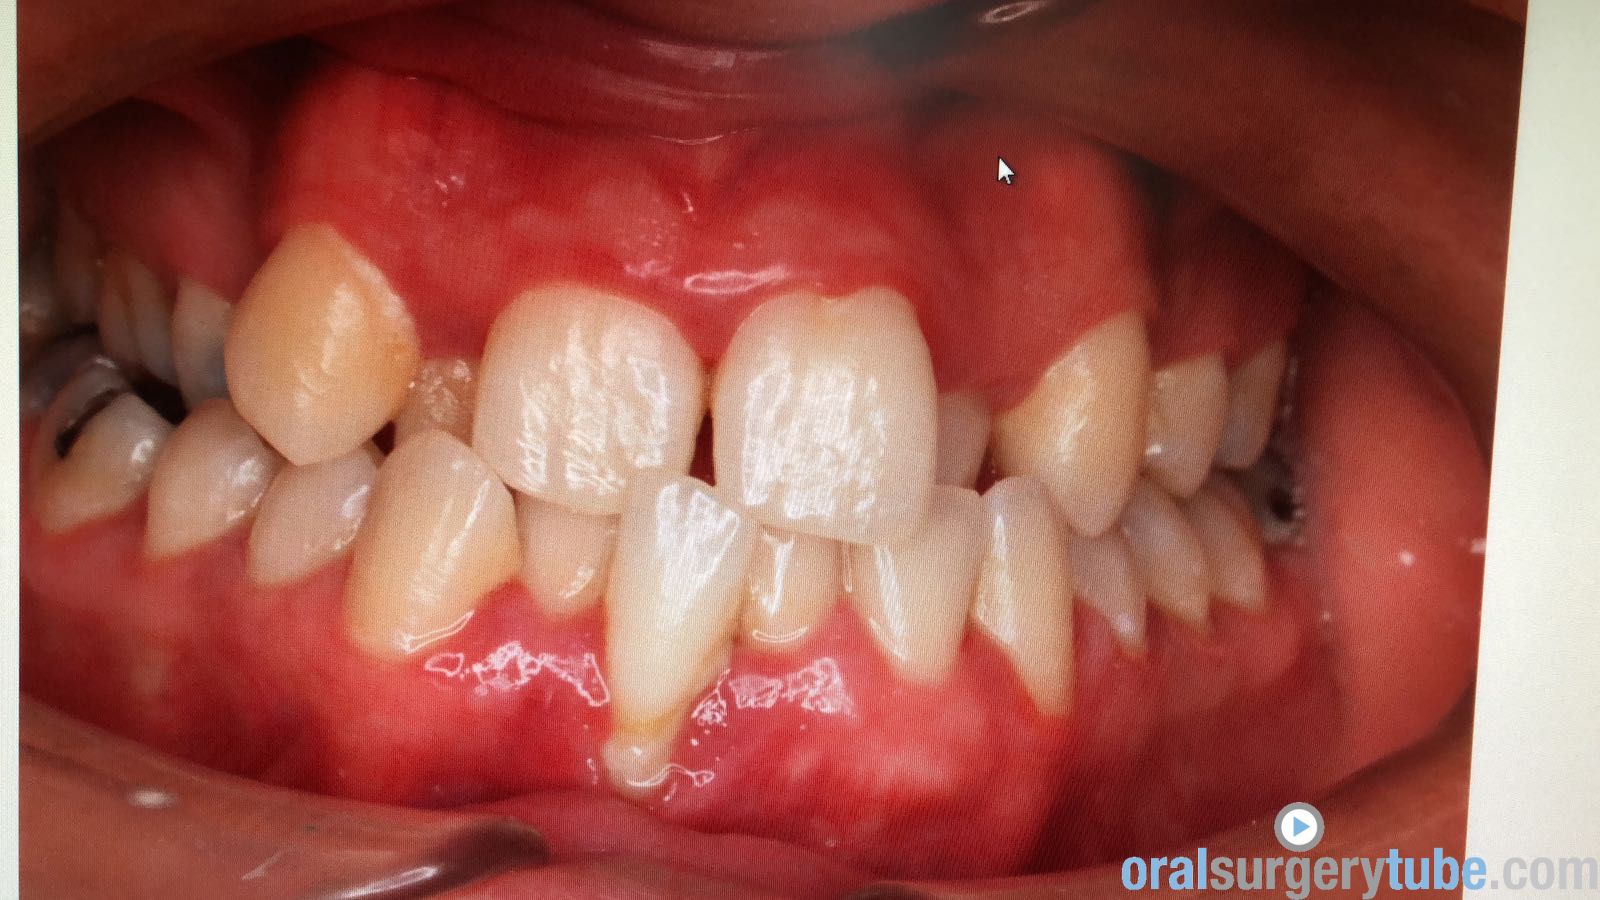

Paciente joven acude para consultar acerca de recesión gingival pieza 31 (clase II Miller). Paciente deja constancia de la importancia de la estética para ella. Hace unos 6 meses, se le realizó cirugía mucogingival con injerto conectivo palatino (la cuál fue fallida, ya que la recesión permanece)... Refiere además cierta molestia al traccionar del labio.

Al movilizar el labio, me transmite la sensación de haber quedado una inserción de fondo de vestíbulo alta... Pienso que podría ser debido a no haber realizado una desinserción muscular al reponer el colgajo coronalmente? (Foto 2). Considero que aún mantiene cierta cantidad de banda queratinizada, pero realmente mínima.

Dado a que se trataría de realizar una "reentrada" o retratamiento (no tengo experiencia hasta la fecha de haber tenido que retratar ningún caso de mucoginigval), agradecería toda opinión acerca de la técnica que más idónea consideréis... Teniendo en cuenta esas posibles adherencias musculares, el biotipo, la demanda estética de la paciente, no sé si lo ideal es tratar con injerto conectivo tipo "técnica bilaminar" y desinsertar la musculatura, o un Injerto de Encía Libre (FGG) y reponer apicalmente la musculatura...

La duda que me surge con el injerto conectivo es si el colgajo me permitiría ser reposicionado coronalmente, teniendo en cuenta esa sensación de "tirantez" actual que describe el paciente. Y la duda de realizarlo con FGG es si conseguiría cubrir la recesión por completo, y si es adecuado para ese solo diente...

Disculpas por la calidad de las fotos, que son algo desenfocadas.